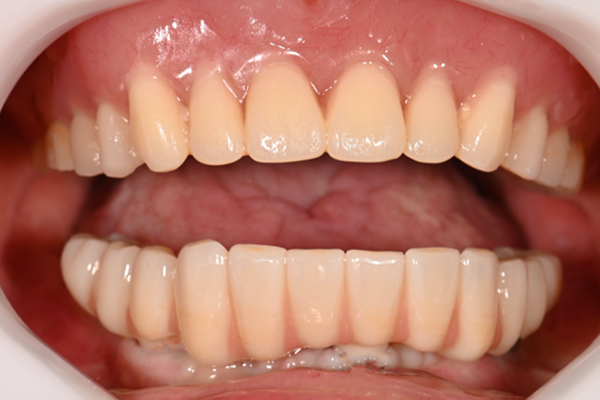

| 主訴 | 全体的にきれいにしたい |

| 治療内容 | 午前中に上下顎共に重度の歯周病、虫歯のため全ての歯を抜歯させていただき下顎はインプラントの土台を3本埋入し歯型を取り午後に上部構造(下顎全ての歯)を装着、上顎は一度総入れ歯を装着させていただきました。 治療が1日で完了しその日のうちに噛めるようになります。 |

| 治療期間 | 2回(1回目に資料取りをさせていただき2回目に下記の全ての治療をさせていただきました。) |

| 治療費 | 250万円 |